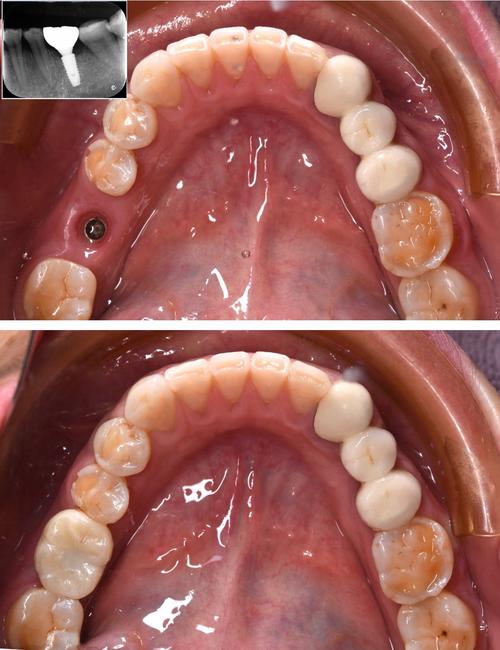

(图片来源网络,侵删)- 挂号: 建议通过南京鼓楼医院的官方渠道(官网、官方APP、微信公众号、电话预约等)提前挂号,选择口腔科或口腔颌面外科,并尽量选择种植牙专科医生或知名专家的号源,知名专家号源可能比较紧张,需提前规划。